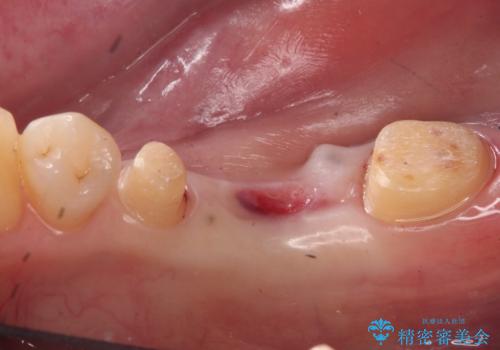

初診時には歯肉が腫れており、膿が出ている状態でした。

また、根の詰め物が根尖孔外(根の先の外の骨の部分)に盛大に漏れ出しており、歯周ポケットと根尖病巣が交通しているような状態でした。

被せ物を外したところ、歯が大変薄くなって割れており、残念ながら残すことはできないと説明しました。

歯がなくなったところに関しては、ブリッジで修復することにしました。

当院は最後まで歯を残せるように、きちんと破折していないかチェックし、患者様に写真を確認していただいたうえで抜歯をするかを相談していきます。